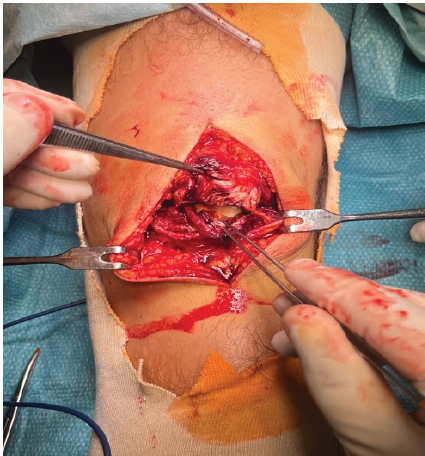

Under subarachnoid anesthesia, surgery was performed in the supine position. A tourniquet was applied for the whole procedure. Bone marrow aspiration was taken from the iliac crest and put in the bone marrow aspirate concentrate (BMAC) centrifuge. A parapatellar incision was performed, and total patellar tendon rupture was reported (Fig. 2).

Figure 2: Intraoperative finding of complete patellar tendon tear.

Notably, also the medial and lateral capsule was teared. First, the tendon sides were attached using non-absorbable sutures, and the anteromedial and anterolateral capsules were reconstructed using the same sutures (Fig. 3).